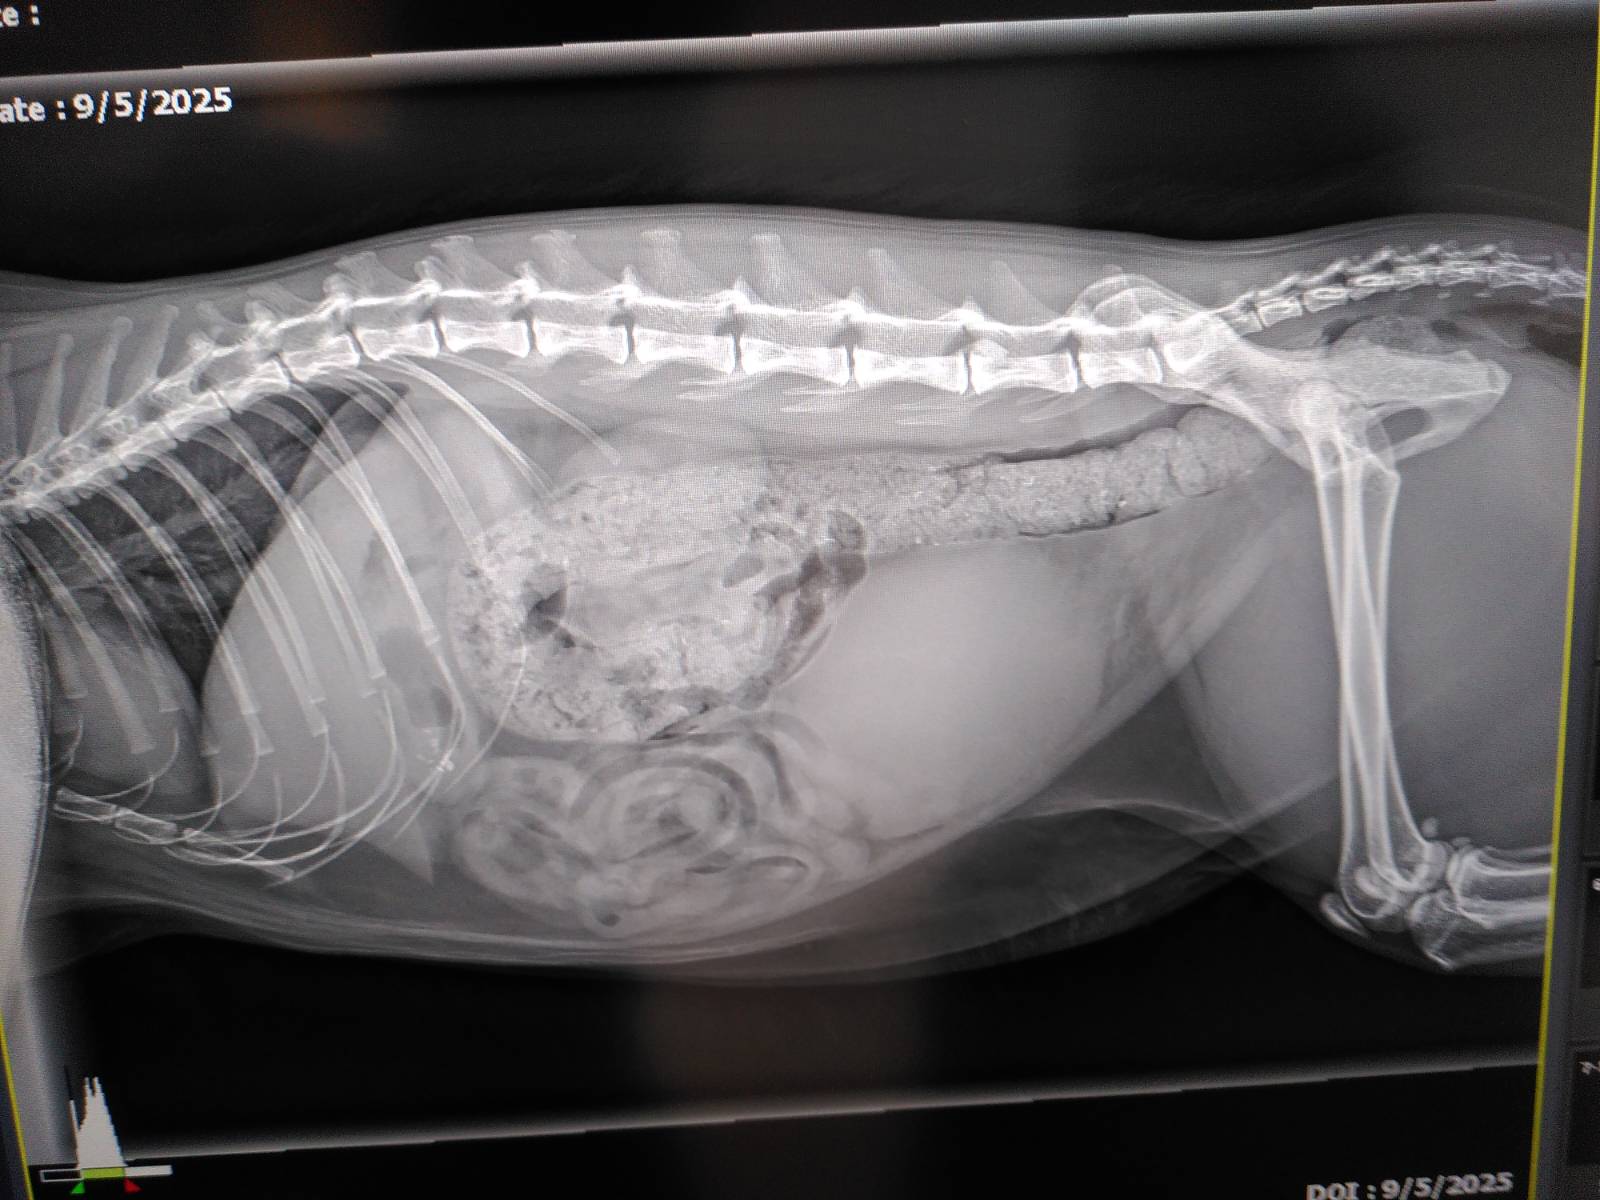

Jeg havde kontaktet den super dygtige dyrlæge/kiropraktor, som behandler Skofus for de udfordringer han har med ryggen. Hun ringede tilbage fredag formiddag og blev sat ind i Chardonnays sag. Hun var helt overbevist om at hans symptomer passede med at “noget” trykkede på nerverne i den bagerste del af lænden, så hun anbefalede at vi fik taget røntgen i to dimensioner af hans lænd. Hun havde for nylig haft en patient med lignende symptomer på grund af gigt, som havde haft god effekt af akupunktur, så jeg nåede lige at få et glimt af optimisme.

Vi tog til dyrlæge og aftalte at han skulle have noget beroligende og have taget billeder af lænden. Jeg var nødt til at køre i stalden fordi der kom smed til min hest. Så stod midt i at hente hest ind fra fold og gøre klar til smed da dyrlægen ringede tilbage med besked om at røntgenbillederne viste en overfyldt blære, helt fuld tarm og en stor massiv indvækst i rygkanalen ved den 6. lændehvirvel. Hun kunne ikke sige noget om det var knogledannelse eller en tumor, men den var så stor at hun ikke mente der var noget perspektiv i yderligere behandling og hun ville anbefale at han blev aflivet inden han nåede at vågne fra bedøvelsen. Så min mand kørte ned og var der da han fik den sidste sprøjte og tog ham med hjem så jeg og de andre katte kunne sige farvel til ham og vi kunne begrave ham ude i vores have, som han elskede.